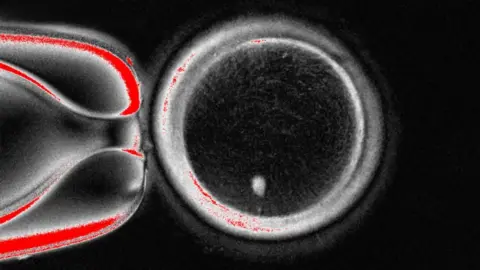

This is then placed inside a donor egg that has been stripped of its genetic instructions.

OHSUHowever, this egg is not ready to be fertilised by sperm as it already contains a full suite of chromosomes.

So the next stage is to persuade the egg to discard half of its chromosomes in a process the researchers have termed “mitomeiosis” (the word is a fusion of mitosis and meiosis, the two ways cells divide).

The study, published in the journal Nature Communications, showed 82 functional eggs were made. These were fertilised with sperm and some progressed onto the early stages of embryos development. None were developed beyond the six-day-stage.